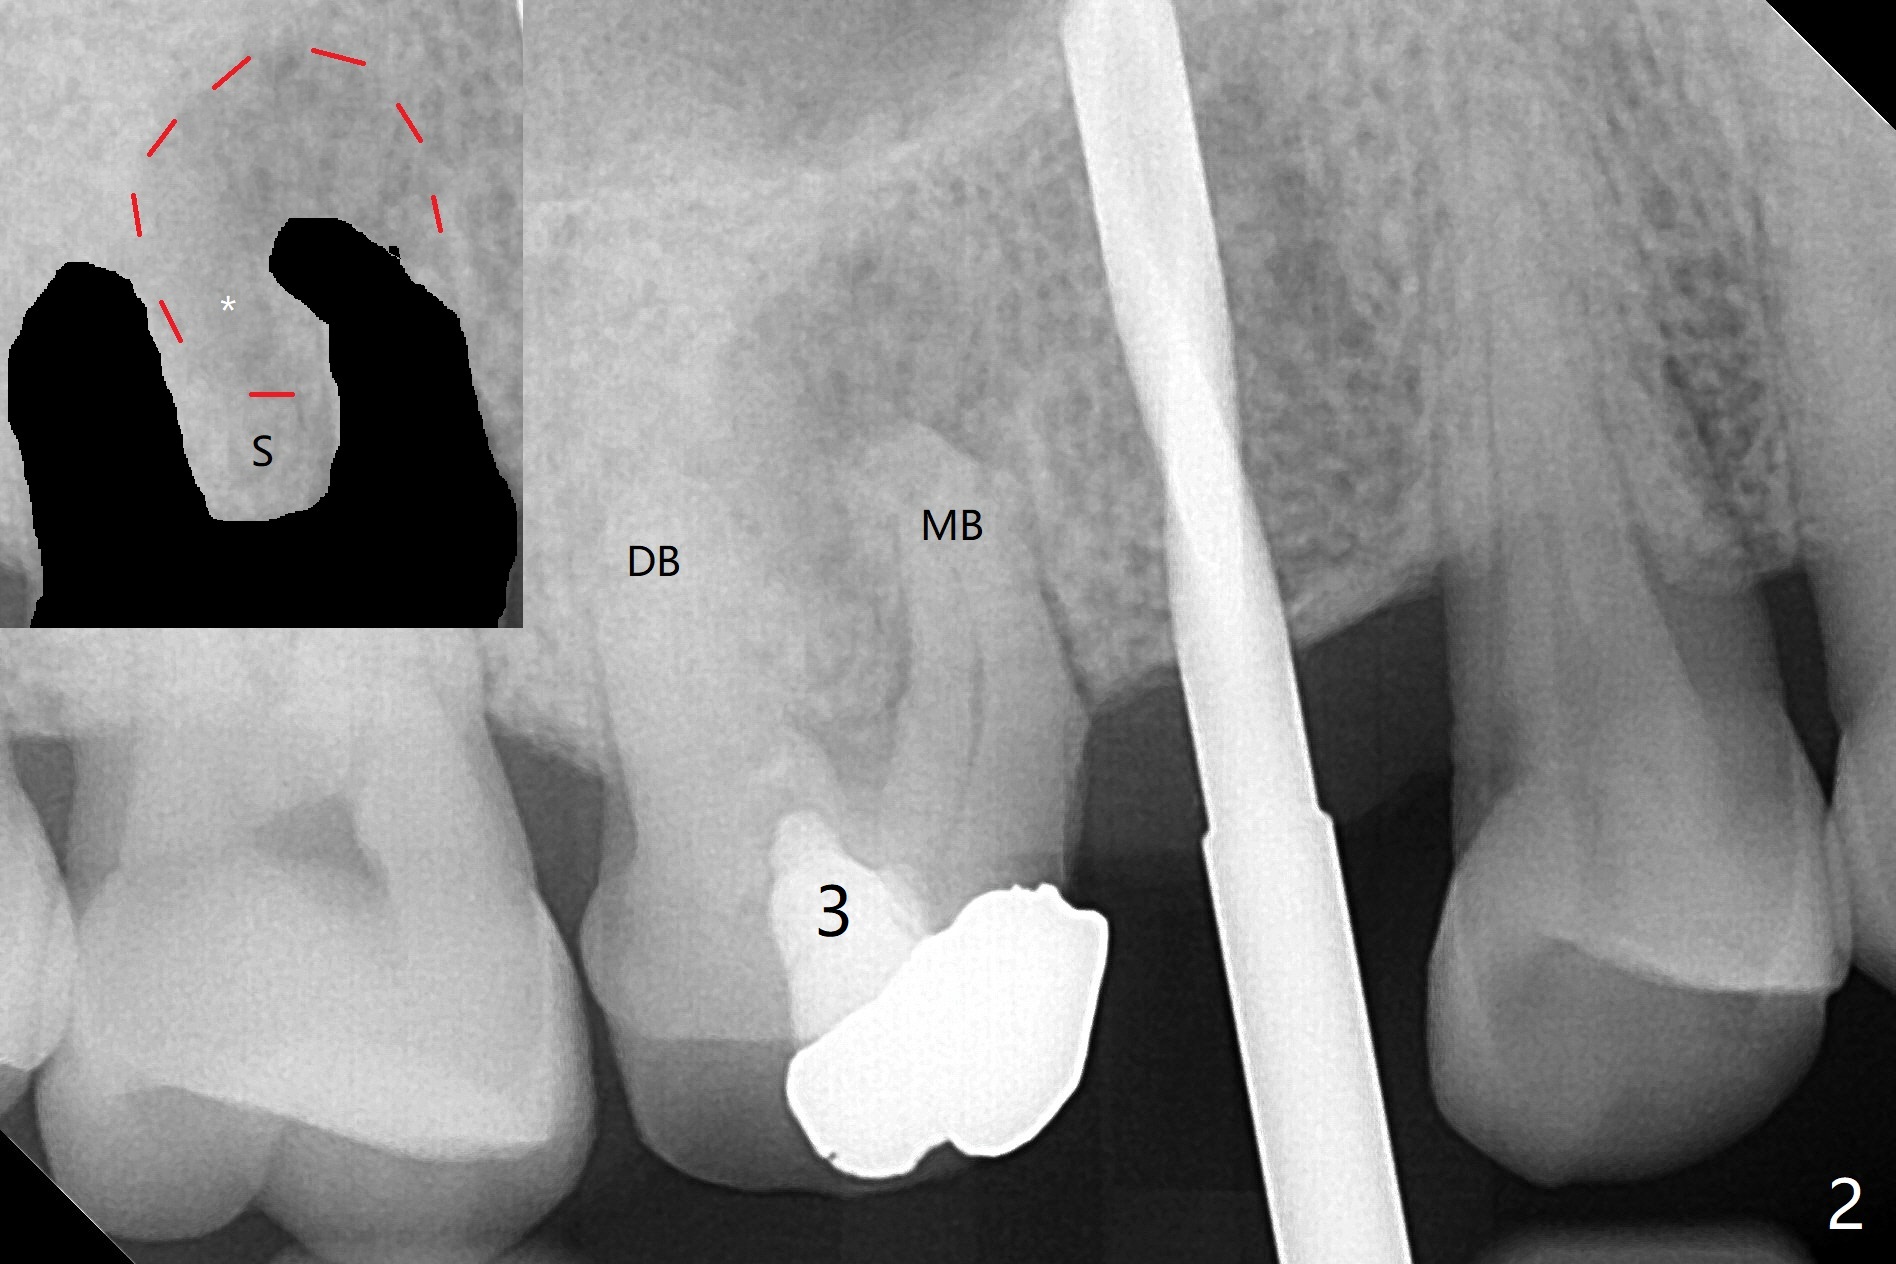

As planned, osteotomy starts at #4 prior to #3 extraction (Fig.1,2). In fact the bone density at the edentulous area is high. Drills are used to finish placing a 4x17 mm tissue-level implant (Fig.3).

A challenge associated with #3 extraction is large amount of granulation tissue apical to the mesiobuccal root (MB, Fig.2 (inset: red dashed line)). To remove the granulation tissue (*) apical to the septum (S), the septum between the buccal roots has to be chiseled. The remaining septum for osteotomy becomes less.